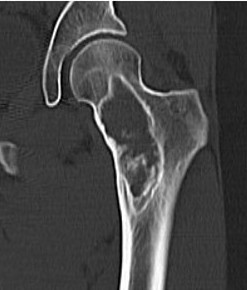

CT

Intramedullary lucent diaphyseal lesion with 'ground glass appearance'

- thinned, slightly bulged cortex

- ± endosteal scalloping

- may have angular deformity / bowing

Coxa vara and Shepherd's Crook deformity of proximal femur

- Shepherd's Crook - anterior bowing of femur